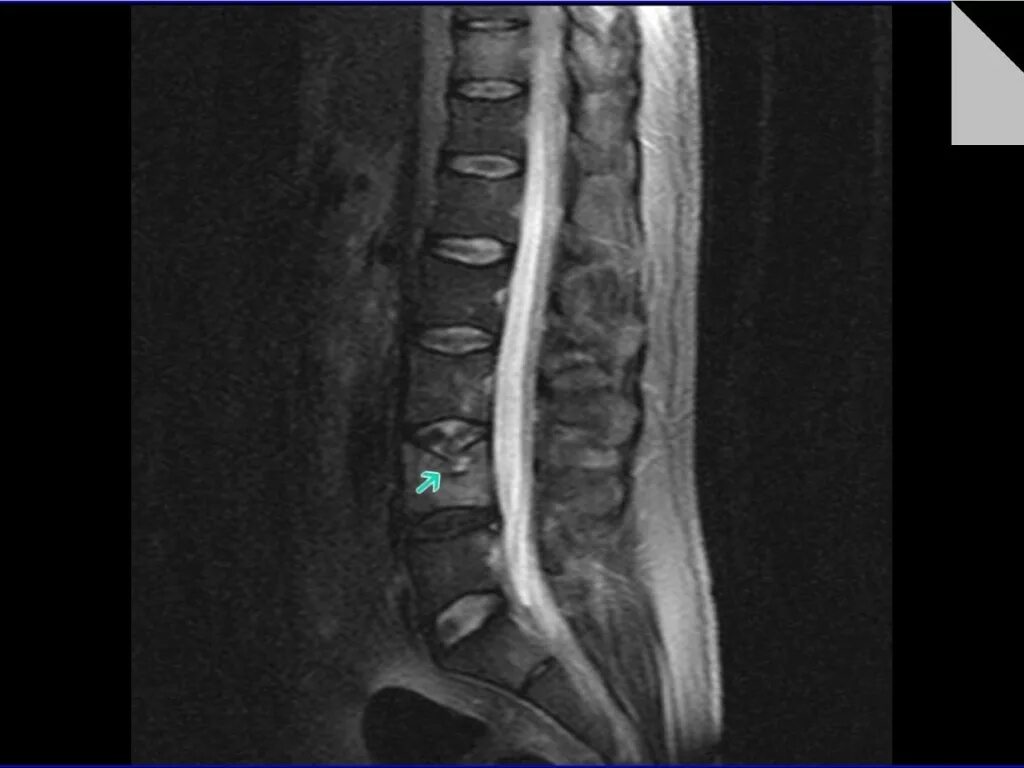

Компрессионный 4 позвонка